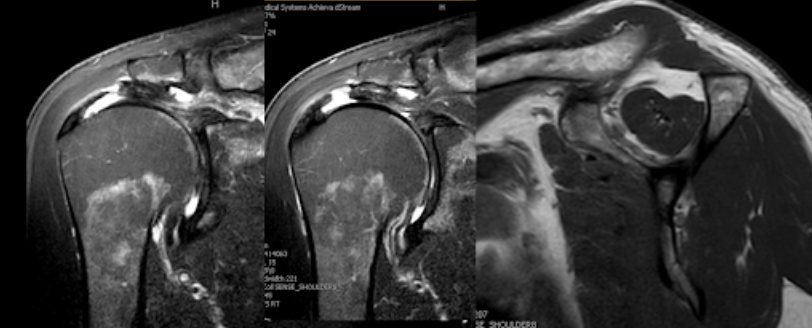

Four recently published articles provide important new information about the ream and run procedure for active patients with shoulder arthritis Those readers interested in learning more can access a discussion of these new articles here: shoulderarthritis.blogspot.com/2026/03/cocr-r…